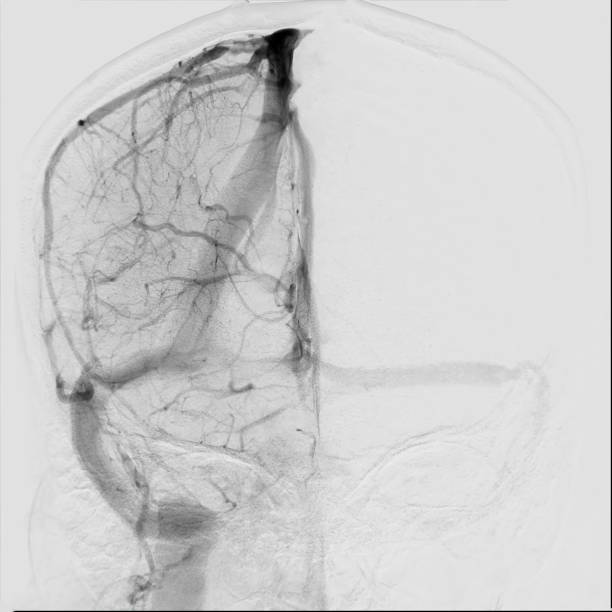

🟢 뇌경색이란 무엇인가요?

뇌경색은 뇌혈관이 막히면서 해당 부위에 혈액이 공급되지 않아 뇌세포가 손상되는 질환이에요.

**‘허혈성 뇌졸중’**이라고도 하며, 전체 뇌졸중의 약 **70~80%**를 차지할 만큼 흔한 형태입니다.

보통은 고혈압, 당뇨, 고지혈증, 흡연, 심장질환 등이 주요 원인으로 작용하죠.